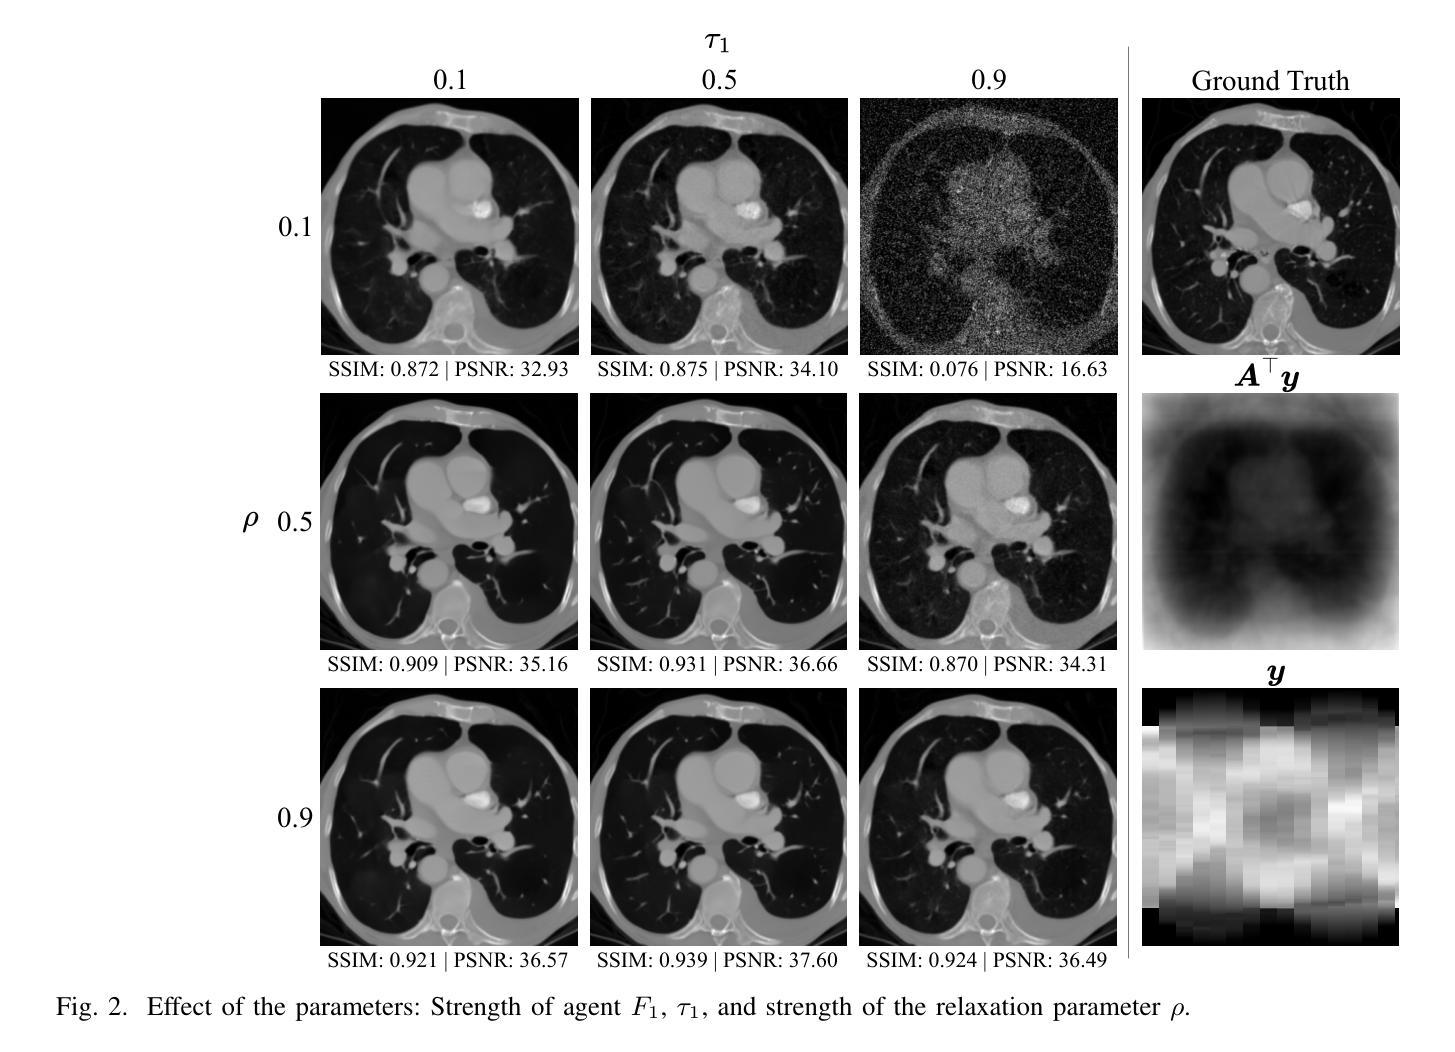

Sparse-view computed tomography (CT) reconstruction is fundamentally challenging due to undersampling, leading to an ill-posed inverse problem. Traditional iterative methods incorporate handcrafted or learned priors to regularize the solution but struggle to capture the complex structures present in medical images. In contrast, diffusion models (DMs) have recently emerged as powerful generative priors that can accurately model complex image distributions. In this work, we introduce Diffusion Consensus Equilibrium (DICE), a framework that integrates a two-agent consensus equilibrium into the sampling process of a DM. DICE alternates between: (i) a data-consistency agent, implemented through a proximal operator enforcing measurement consistency, and (ii) a prior agent, realized by a DM performing a clean image estimation at each sampling step. By balancing these two complementary agents iteratively, DICE effectively combines strong generative prior capabilities with measurement consistency. Experimental results show that DICE significantly outperforms state-of-the-art baselines in reconstructing high-quality CT images under uniform and non-uniform sparse-view settings of 15, 30, and 60 views (out of a total of 180), demonstrating both its effectiveness and robustness.